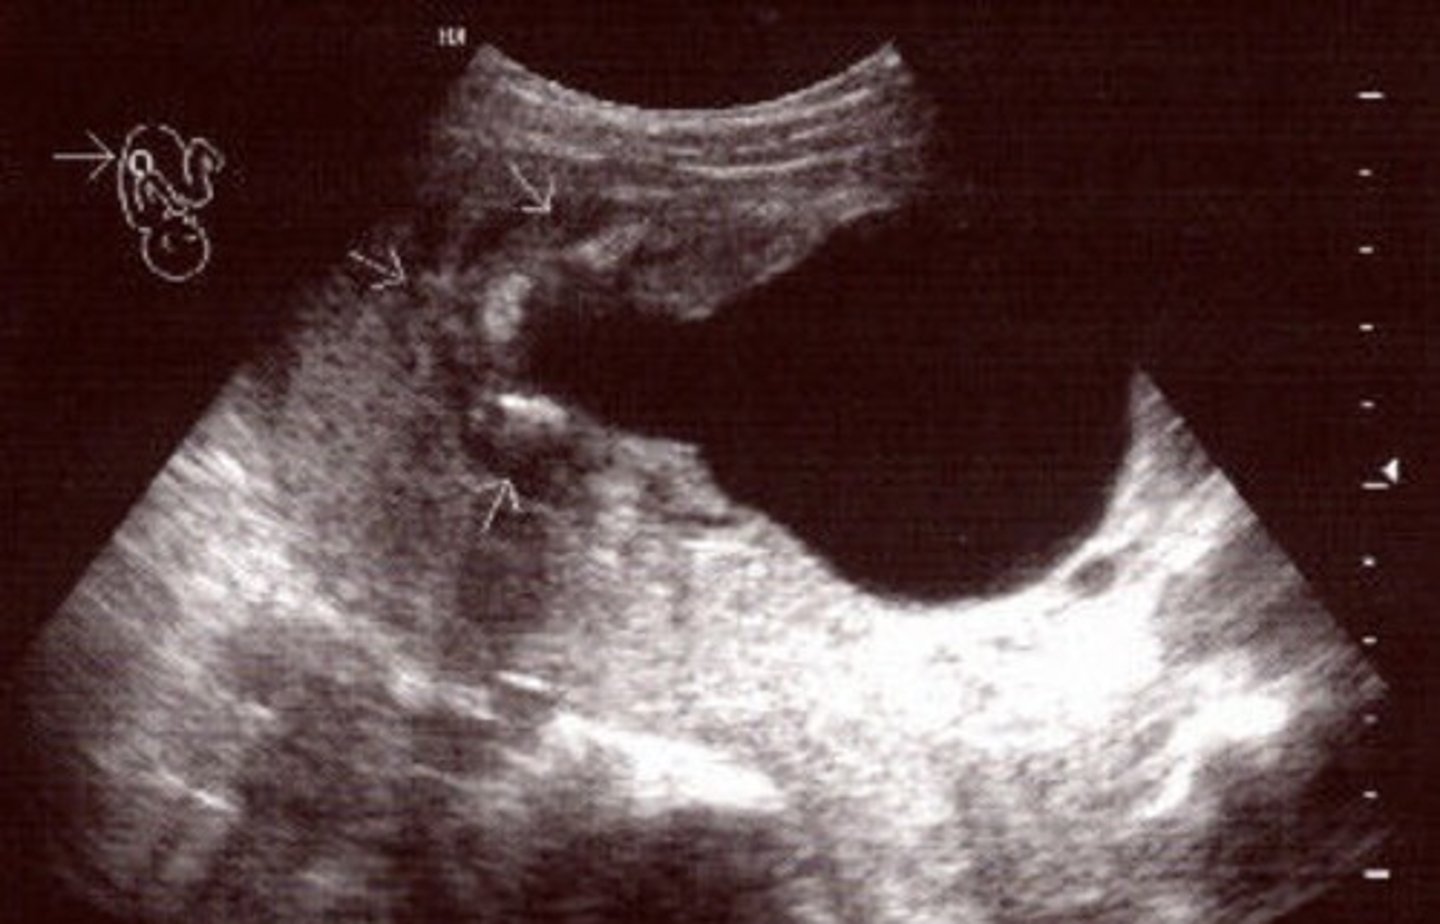

Potter's Syndrome Type II - Multicystic Dysplastic Kidney Disease

Kidney tissue is replaced by cysts - multiple and variable in size

Usually unilateral

Enlarged kidneys

Ill-defined walls & parenchyma/pelvis